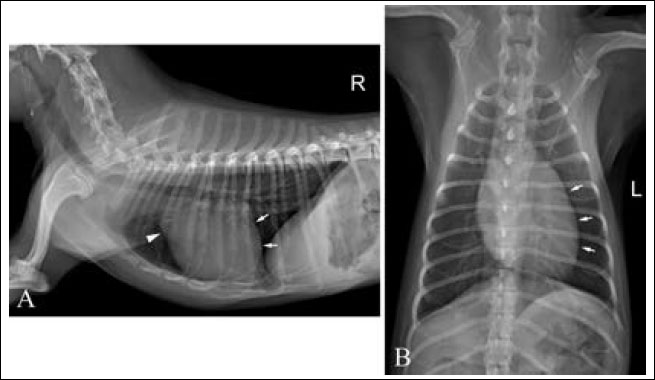

A 2–year-old intact female Shih-tzu dog weighing 3.6 kg presented with a history of mild exercise intolerance. The owner was aware that the patient had an abnormal cardiac murmur since she was 3 months old. Auscultation revealed a decrescendo pandiastolic murmur at the left sternal edge. No abnormalities were detected in the complete blood count, serum biochemical analysis, or electrolyte examination. Thoracic radiography revealed mild left ventriculomegaly and bulging of the ascending aorta. The cardiac size is within normal range with the value of vertebral heart score of 10.0 and vertebral left atrial score of 2.2 (Fig. 1).

Fig. 1. Right lateral (A) and ventrodorsal (B) thoracic radiographs. mild left-sided enlargement of the cardiac silhouette (white arrows) and mild bulging of ascending aorta (arrowhead) are seen. The cardiac size is within normal range with the value of vertebral heart score of 10.0 and vertebral left atrial score of 2.2.